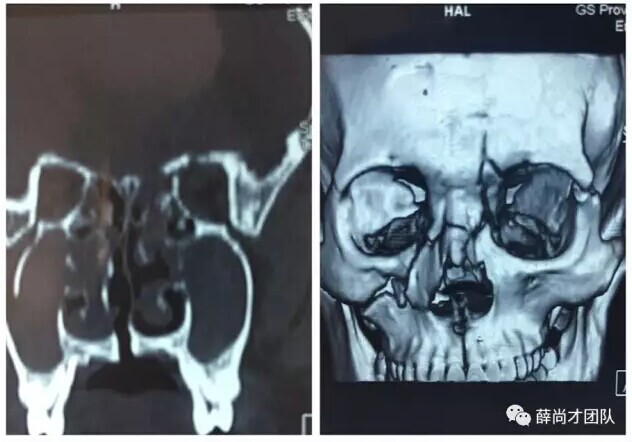

甘肃省二院眼科开展经眼眶视神经减压术使许多外伤失明的患者重见光明------2017-04-28 发布时间:2017-04-28 来源: 作者:

本文转自:薛尚才团队